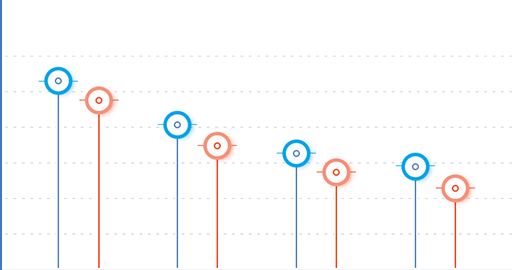

Dank intelligenter Formel und Komponenten, die keine Nebenwirkungen verursachen

Arnica montana, Boswellia Serrata

bietet entzündungshemmende, antiekchymosische und analgetische Eigenschaften. Es verfügt auch über antiseptische und vasoprotektive Wirkung.

Cupressus sempervirens

zeigt eine schwache antiseptische Wirkung, kühlt die Haut und hat auch eine lokalanästhetische Wirkung.